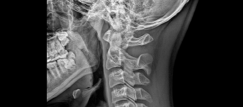

목디스크는 디스크라는 뼈와 뼈 사이의 공간에 위치한 수핵이 나와 경추 신경을 압박하여 발생하는 질환입니다. 목디스크는 인체의 다른 부위에 비해 가장 많이 발생하는 질환이며, 나이가 들면서 더욱 빈번하게 발생하게 됩니다. 이번 글에서는 목디스크의 증상 3가지를 알아보겠습니다.